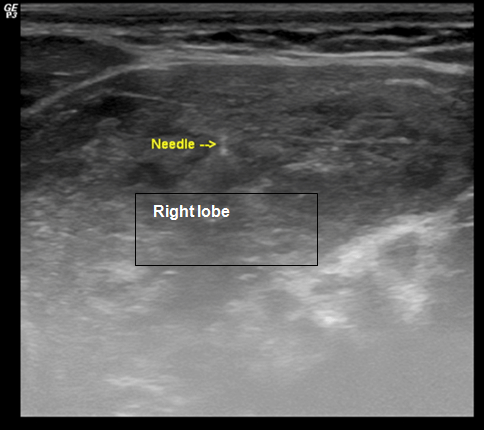

A 32-year-old female with a history of Hodgkin’s lymphoma presented with a two week history of thyromegaly. Hodgkin’s lymphoma was diagnosed at the age of 29 years and was treated with two cycles of ABVD (doxorubicin, bleomycin, vinblastine, and dacarbazine) chemotherapy and radiation therapy which was 2000 cGy in 10 fractions to the left lower cervical and supraclavicular nodal regions. One year after her diagnosis of lymphoma, she was considered to be in remission. She was also diagnosed with hypothyroidism with elevated anti-thyroid peroxidase antibody levels at the age of 29 years and treated with levothyroxine. At the age of 32 years , she developed thyromegaly causing dysphagia and hoarseness over a two-week interval. Physical examination revealed thyromegaly but no cervical lymphadenopathy. Due to her history of lymphoma positron emission tomography (PET) imaging was performed and demonstrated increased, diffuse fluorodeoxyglucose (FDG) uptake in the thyroid with right lobe being larger than the left (Figure 1). Ultrasound was also performed and showed thyromegaly especially on the right side but no thyroid nodules (Figure 2). Fine needle aspiration (FNA) of the right lobe was performed with flow cytometry of the needle washings (Figure 3). Flow cytometry of the needle washings did not show any clonal or aberrant populations of lymphocytes making lymphoma unlikely. Cytologic examination showed a background of lymphocytes and lymphoid stroma consistent with Hashimoto’s thyroiditis. Over the next two months the patient’s thyromegaly, dysphagia, and hoarseness gradually resolved. She continued to be treated with levothyroxine for her hypothyroidism related to Hashimoto’s thyroiditis.

Figure 1: Coronal view of positron emission tomography imaging showing increased, diffuse fludeoxyglucose uptake within the thyroid. The thyroid has been circled.